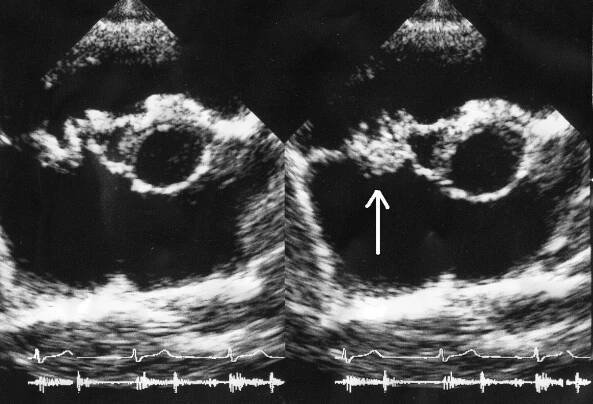

Endokarditida - vegetace na aortální chlopni na TEE

Infekční endokarditida je zánět vnitřního povrchu srdce neboli endokardu, který je způsobený mikroorganismy a postihuje zejména srdeční chlopně.